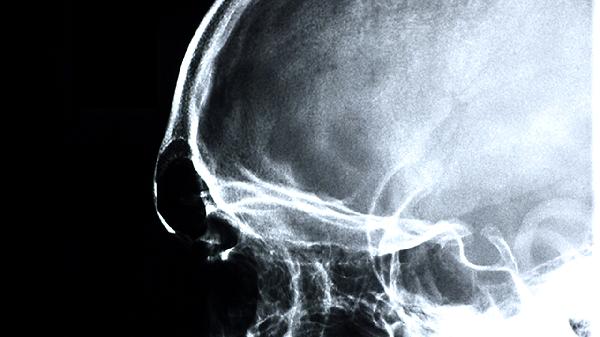

心房颤动、心力衰竭等心脏疾病可能导致心输出量下降,影响脑部供血。患者可能伴随心悸、气短等表现,可通过心电图检查确诊。治疗需针对原发病使用华法林钠片、酒石酸美托洛尔片、地高辛片等药物,严重者需考虑心脏起搏器植入术。

脑供血不足患者应保持规律作息,每日进行30分钟有氧运动如快走或游泳,饮食注意低脂低盐,多摄入深海鱼、西蓝花等富含不饱和脂肪酸和抗氧化物质的食物。避免突然起身或过度劳累,气候变化时注意头部保暖。若症状反复发作或加重,应及时进行经颅多普勒超声或脑血管造影检查,明确病因后针对性治疗。